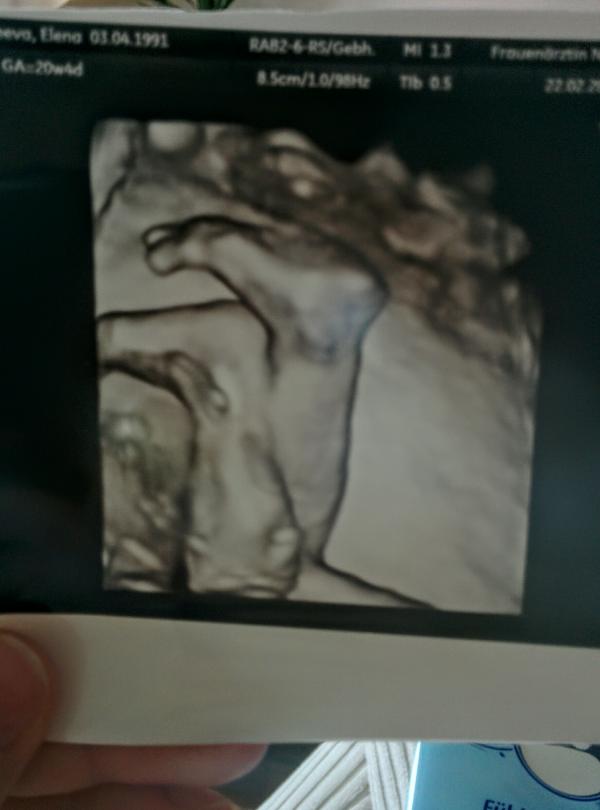

Привет! Сегодня узнали пол🙈- девочка. Радости полные штаны) не было какого-то особого желания, но с самого начала думала, что девочка 100%. Вот такое фото нам врач вручила после узи😍